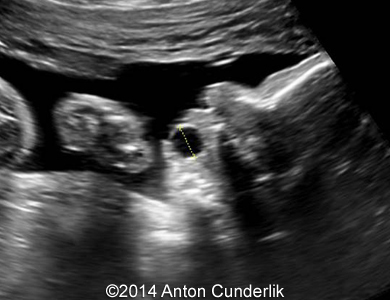

Image 2, 3, 4, 5, 6, 7: 30 weeks of gestation; the images show cystic structure within the fetal tongue that later turned out to be thyroglossal cyst.